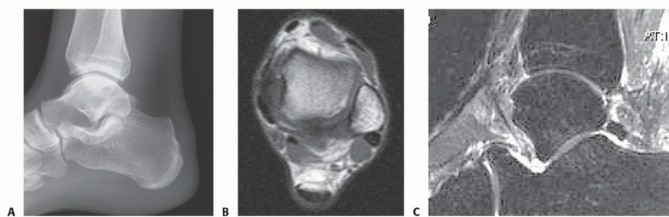

DEFINITION Osteochondral lesion of the talus (OLT) may cause significant pain and mechanical symptoms in the …

DEFINITION The term osteochondral lesion of the talus (OLT) refers to any pathology of the talar articular ca…